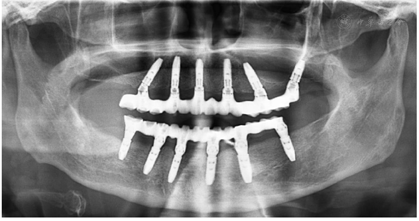

治疗过程:(1)术前准备:①藻酸盐取初印模,制作个性化托盘(图4);②用个性化托盘取硅橡胶终印模,灌制终模型;③制作光固化树脂

架;④排牙,制作放射导板(图6A);⑤试戴放射导板(图6B~D),拍摄两次CBCT(患者佩戴放射导板拍摄CBCT以及放射导板单独拍摄CBCT)。(2)方案设计:①将两次CBCT获取的DICOM数据导入种植设计软件重叠(图7),以修复为导向指导上下颌种植体位置摆放(图8、图9);②生成并打印手术导板(图10)。(3)利用手术导板和导板锁,翻制模型,制作临时修复体(图11)。(4)一期手术过程:铺巾消毒,局麻后拔除上下颌余留牙,搔刮拔牙窝内炎性肉芽组织,于34-36、44-46区牙槽嵴顶近远中向切开牙龈,翻瓣。就位并固定手术导板,于11、13、16、22、25、26、32、34、36、42、44、46定点,按术前设计方案植入NobelParallelTM ConicalConnection种植体。除26区种植体外,其余种植体初期稳定性均达到35N.cm以上,就位复合基台,戴入保护帽,修整牙龈黏膜,缝合牙龈(图12A~F)。术后拍摄全景片(图13)。次日复诊,取下保护帽,戴入预制的临时修复体,调合(图12G)。

治疗结果:术后3个月全景片显示种植体骨结合良好(图14)。26牙行二期手术,就位复合基台,戴入保护帽。两周后,取下临时修复体,制取上下颌硅橡胶印模,利用临时修复体交叉上

术后一年随访:拍摄全景片显示种植体周围骨结合良好,边缘骨高度稳定(图19)。义齿外形无变化,下颌义齿前牙区舌侧面见牙结石。